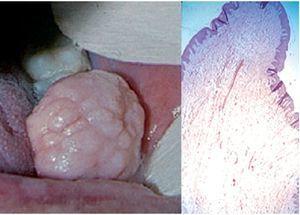

Tumor mixto de glándulas salivales o adenoma pleomorfo. Es una proliferación neoplásica benigna relativamente frecuente en la parótida, pero que con mucho menor frecuencia puede desarrollarse a partir de las glándulas salivales menores. Suele verse a partir de los 40 años, y sin preferencia de sexos. Se trata de un tumor de crecimiento lento, consistencia dura y tamaño < 2 cm, aunque excepcionalmente pueden ser bastante mayores, generalmente en labio superior o paladar. La histopatología, con componente epitelial y glandular con células de aspecto diverso en estroma mucoide y cartilaginosa, es imprescindible para el diagnóstico. Mucho más raro aún es el mioepitelioma. En esta lesión todas las células son mioepiteliales, pero se la considera una variedad de adenoma pleomorfo (fig. 12).

Figura 12. Tumor glandular benigno, clínicamente inespecífico, en el que la histopatología demuestra la variedad de celularidad y estroma en el adenoma pleomorfo (A), y la presencia masiva de celúlas mioepiteliales en el mioepitelioma (B).